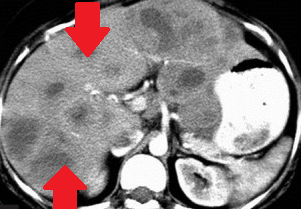

Red arrows – Rectal stromal tumor. Multiple liver metastases (Courtesy Dr. V. Penopoulos)